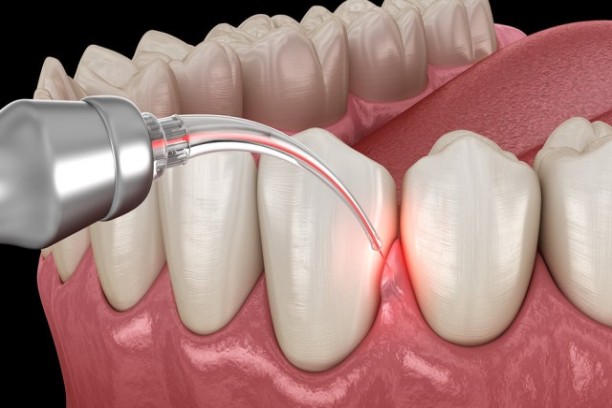

Flap Surgery

Treats advanced gum disease by cleaning and repositioning gums

Gingivectomy

Removes excess or infected gum tissue to improve gum health.